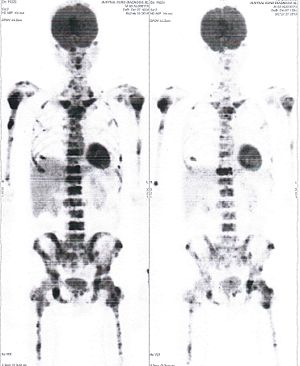

CASE NO: 3 (PROSTATE CANCER)

A middle-aged man with castration resistant prostate cancer, having failed all currently available cancer treatment, was very weak, and getting worse every day. The PET/CT scan showed he had massive bone metastases. After a few treatment, all the bone metastases went into remission. About 6 months later, he is still in remission.

CASE NO: 4 (PROSTATE CANCER)

A middle-aged man with castration resistant prostate cancer and massive bone metastases, failed all currently available cancer treatment, including with the new and expensive drug XTANDI. After a few treatment, most of the bone metastases went into remission, and the remaining ones are less active. Treatment will continue. Cases no: 3 and 4 show that terminal prostate cancer today can be cured with our new cancer treatment.